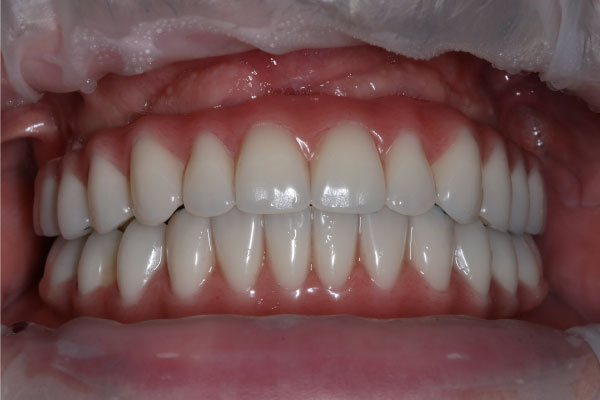

Имплантация зубов: фото "До" и "После"

All-on-4

All-on-6